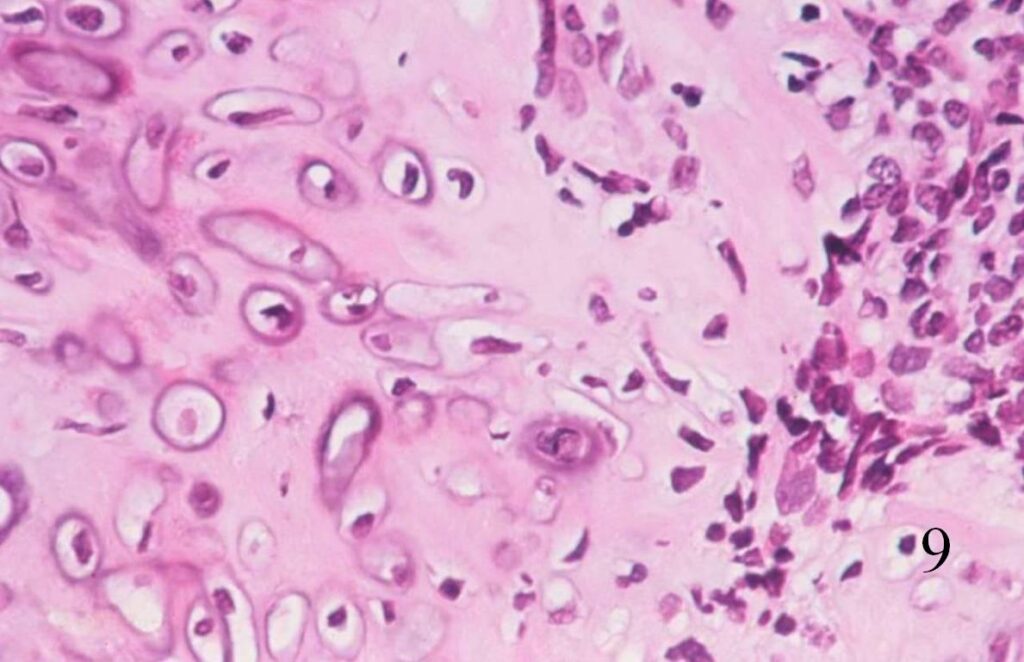

Extraskeletal Mesenchymal Chondrosarcoma (Fig. 8-10)

• Abundant small round blue cells

• Undifferentiated

• Round to elongate or spindle nuclei

• May grow in sheets or nodules, surround by fibrous tissue

• Usually proliferate around narrow vessels and pericytic sinusoidal vessels

• Islands of cartilage, may be calcified or ossified

Fig. 9

Fig. 8-10 Low (Fig. 8) and high power (Fig. 9) magnification of a mesenchymal chondrosarcoma shows cartilaginous areas and a mesenchymal component.

Fig. 10. High power magnification of mesenchymal area shows an area of undifferentiated small round blue cells.